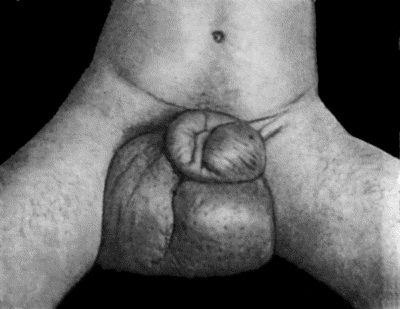

97.Elephantiasis in a woman æt. 45 387

98.Elephantiasis of Penis and Scrotum 388